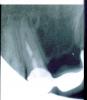

Архиус Опубликовано 1 апреля, 2009 Поделиться Опубликовано 1 апреля, 2009 Добрый день. Хочу узнать мнение опытных врачей, необходимо ли перелечивать данный зуб (см. снимок.) И что вобще вы можете сказать о его состоянии. Ссылка на комментарий

Д.С. Опубликовано 1 апреля, 2009 Поделиться Опубликовано 1 апреля, 2009 Добрый день. Хочу узнать мнение опытных врачей, необходимо ли перелечивать данный зуб (см. снимок.) И что вобще вы можете сказать о его состоянии.Без вопросов. Распломбировать канал, лечить периодонтит. Ссылка на комментарий

Большой Зеленый Опубликовано 1 апреля, 2009 Поделиться Опубликовано 1 апреля, 2009 Перелечивать однозначно! Ссылка на комментарий

АНРОША Опубликовано 1 апреля, 2009 Поделиться Опубликовано 1 апреля, 2009 Добрый день. Хочу узнать мнение опытных врачей, необходимо ли перелечивать данный зуб (см. снимок.) И что вобще вы можете сказать о его состоянии.Перелечивать обязательно. Состояние не самое ужасное...пока... но это вопрос времени. С лечением не затягивайте. Удачи! Ссылка на комментарий

zybnaya feya Опубликовано 2 апреля, 2009 Поделиться Опубликовано 2 апреля, 2009 А никому не кажеться что там перелом? Нужно в другой проэкции сделать снимок Ссылка на комментарий

Снежана Опубликовано 2 апреля, 2009 Поделиться Опубликовано 2 апреля, 2009 Да вроде нет перелома, но еще одна проекция лишней не будет. Ссылка на комментарий